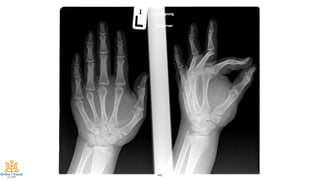

Case #2

47

15-year-old

Mass at thenar area and wrist

Progressive numbness of thumb,

index and middle finger

48

49

50

51

Final Diagnosis:

Lipofibromatous Harmatoma